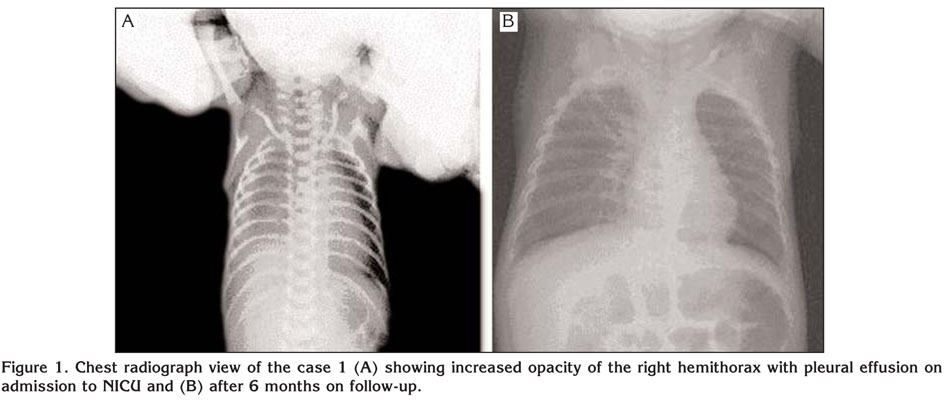

İki yenidoğanda izole doğumsal plevral efüzyon

İki yenidoğanda izole doğumsal plevral efüzyon from www.tuberktoraks.org